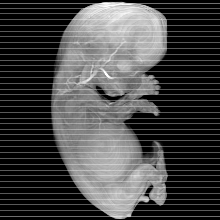

Human Embryo

Carnegie Stage 23 (56 post-ovulatory days)

About Carnegie Stage 23

Most embryos at stage 23 are approximately 56-57 postovulatory days old and measure 23-32 mm in length. Distinguishing criteria for this stage include fusion of the eyelids at the medial and lateral margins, clear distinction of the subdivisions of the upper and lower limbs, the forearms appear at or above the level of the shoulders, the superficial vascular plexus of the head is very close to the vertex, and the external genitalia are well developed but not always sufficiently to distinguish the embryo's sex.

(NOTE: These specimens are late stage 23.)

MRI Slice Selector